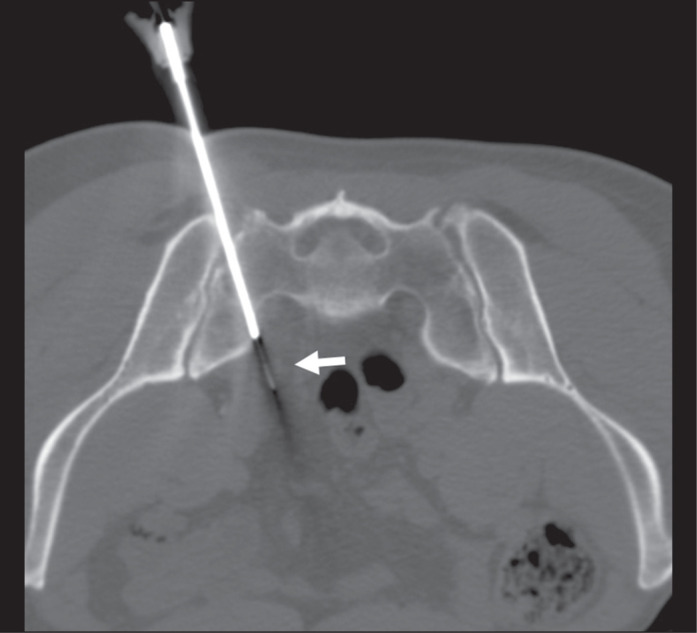

Computed tomography-guided preoperative charcoal tattooing in patients with recurrent prostate cancer after prostatectomy and undergoing pelvic salvage lymphadenectomy.

Abstract Image